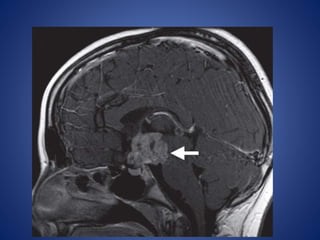

Germ Cell Tumor

Germ cell tumors of the CNS arise in the pineal region, sellar-

suprasellar region, basal ganglia.

Imaging Features.—

• The imaging characteristics of germ cell tumor are highly

variable, including T1 and T2 signal heterogeneity as well as a

variable degree of contrast material enhancement of its solid

elements.

• Germinomas may diffusely enhance.

• Heterogeneity is seen in nongerminomatous germ cell tumors

and may be secondary to intratumoral hemorrhage.

• Cysts may be seen in both germinomas and nongerminomatous

germ cell tumors.

• Synchronous tumors in the pineal and suprasellar regions may occur.

• Dissemination is not uncommon in germ cell tumors, and screening of the

entire neuroaxis should be performed.

• #20 Suprasellar germinoma in an 8-year-old girl. (a) Coronal T2WI reveals a heterogeneous mass with hyperintense cystic spaces in the suprasellar region (arrow)

• #21 (b) Axial T1-weighted image reveals an isointense mass with hypointense cystic areas (arrow) splaying the cerebral peduncles

• #22 enhancement of the solid components of the mass (arrow)